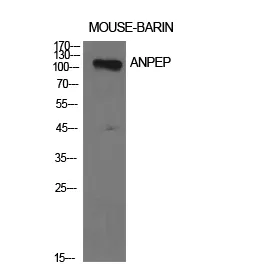

CD13 Rabbit Polyclonal Antibody

Cat: APRab08201

Size1:50μl Price1:$118

Size2:100μl Price2:$220

Size3:500μl Price3:$980

Size2:100μl Price2:$220

Size3:500μl Price3:$980